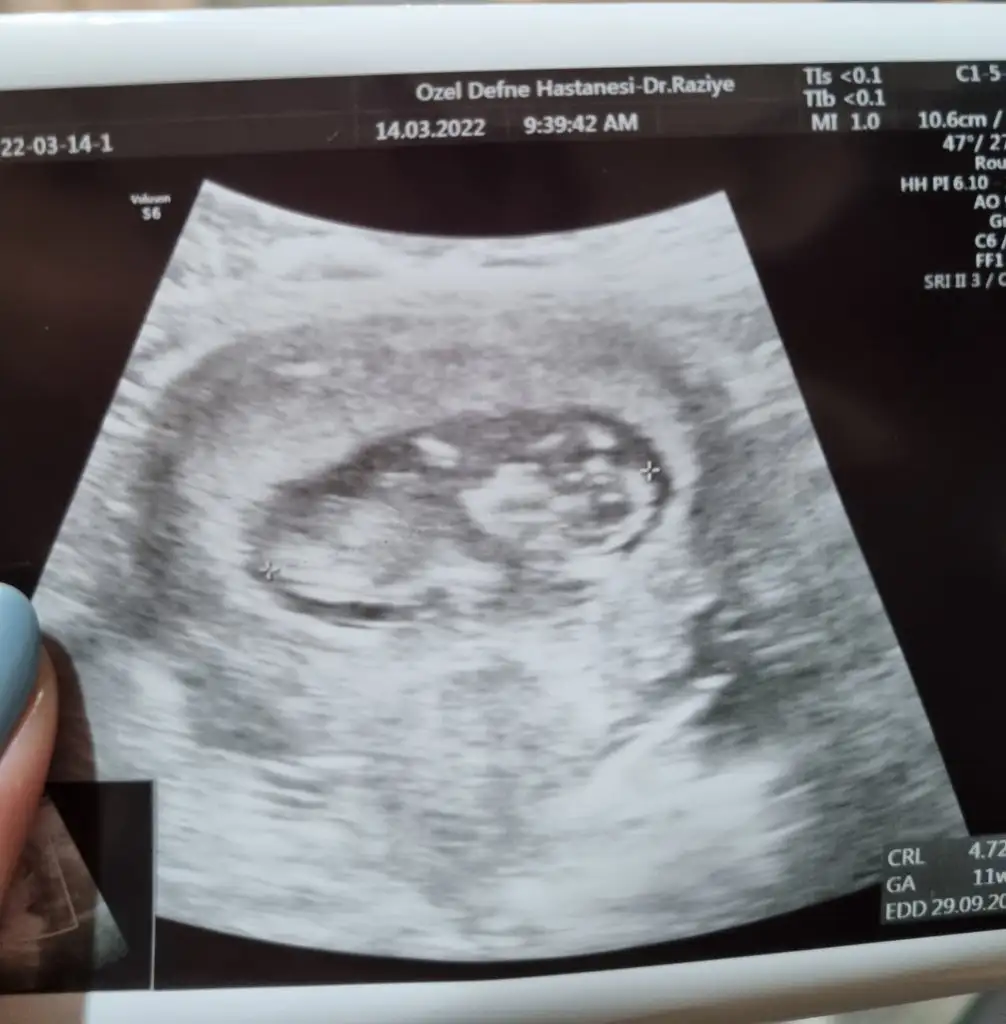

İlk dediki güzel görüntü alabilirsem şimdi bakarım ikili test için olmazsa haftaya gelirsin dedi. İlk minnoş uyuyodu hiç kıpırdamadan duruyordu öylesonra şımarık bakıldığını anladı başladı kaymaya

Elini kolunu gördüm birden hareket etmeye başladı kıpır kıpır doktor maşallah çok hareketli güzel dedi

11+2ydim bugün 11+4 çıktı ense kalinligina bakti 1.13 çıktı o da normalmiş herhalde